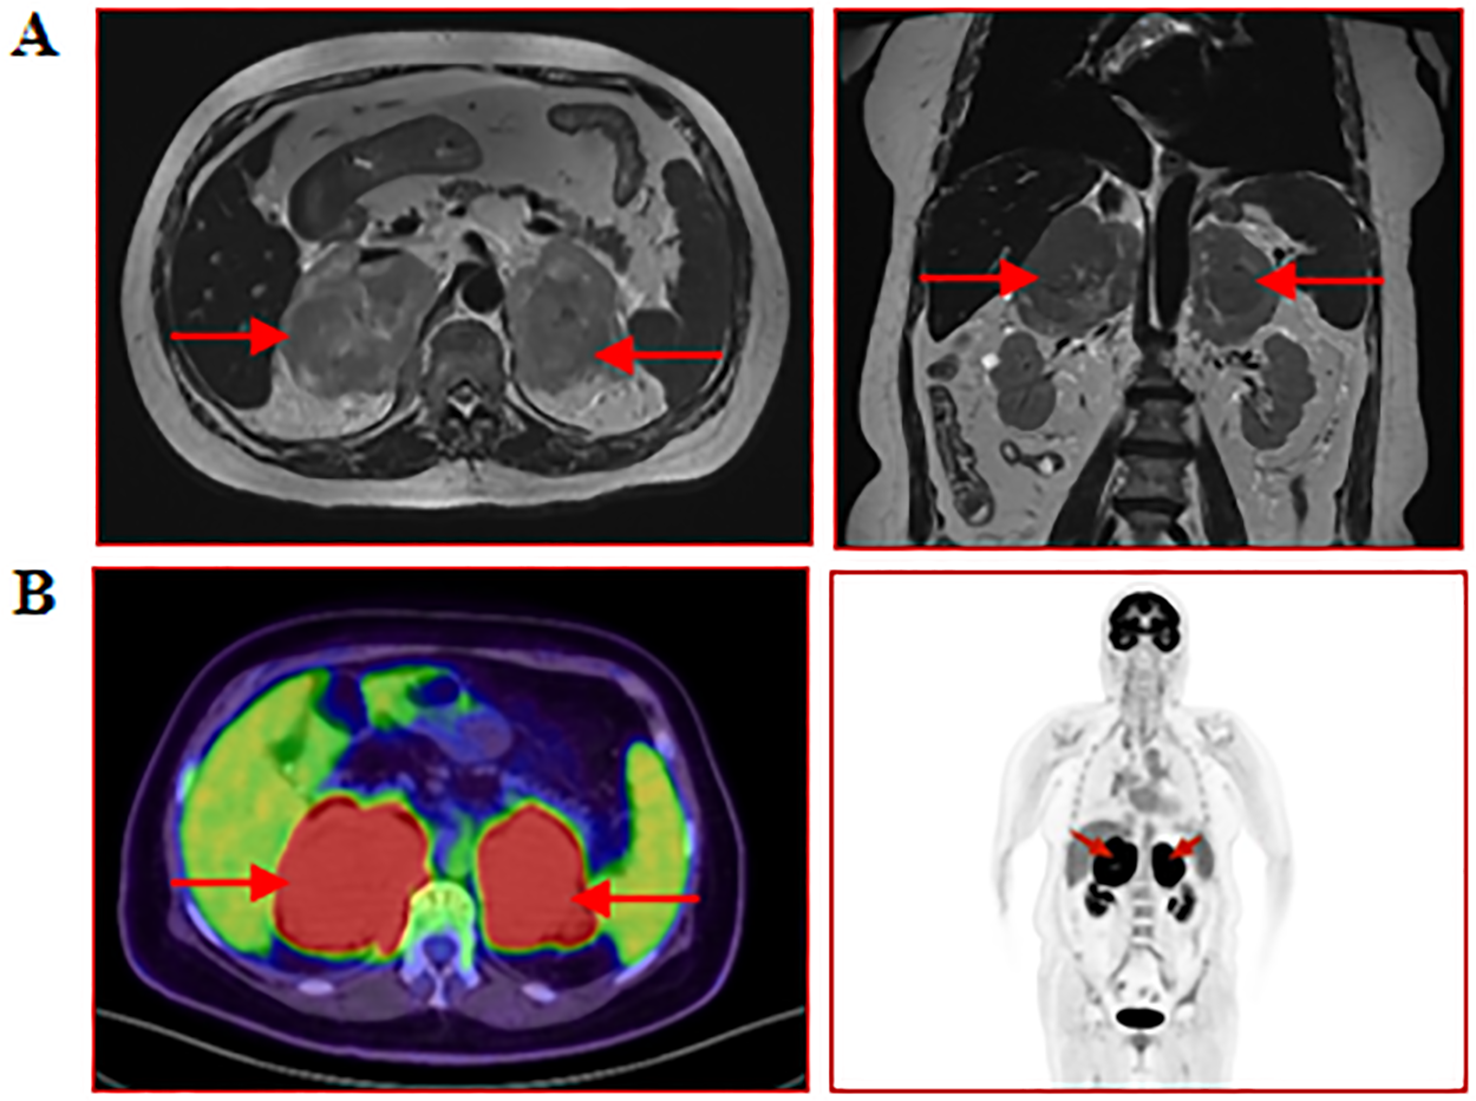

A 77-year-old female patient was admitted to another hospital due to afternoon fever, night sweats, nausea, vomiting, poor appetite, abdominal distension, abdominal pain, dizziness, fatigue, listlessness, insomnia, and weight loss for 20 days. The patient’s QuantiFERON-TB Gold(QFT) test was positive. Adrenal MRI revealed that the left and right sizes were approximately 73×73×51mm and 79×87×63mm, respectively. T1WI showed a slow signal, T2W, fat-suppression T2W showed an isointense and slightly hyperintense mixed signal, and an enhanced scan showed no noticeable enhancement (Figure 3A). Positron emission tomography/computed tomography (PET/CT) showed a soft tissue density mass of 67×47mm and 83×52mm in the left and right adrenal regions, respectively, with a flocculent blur surrounding it, and increased FDG metabolism with a max value of 32.6 to 33.6 (Figure 3B). The patient was treated with anti-tuberculosis therapy. There was no significant improvement in symptoms after 2 weeks of treatment. He subsequently visited our hospital; the laboratory test results are shown in Table 2. A right adrenal gland puncture biopsy suggested antacid staining (-) and PAS staining (-). The immunohistochemistry results show positivity for CD20, CD79a, Ki-67 (90%), Bcl-2, Bcl-6, MUM-1, C-myc, CD15, P53, CD22, and CD19, while CD3, CD5, CD10, ALK, CD30, HHV8, CD38, CyclinD1, and EMA are negative (Figure 4). In situ hybridization: EBER(-).FISH: The BCL6 isolation probe was negative, with a total number of 100 cells, of which 1% were isolated cells; the BCL-2 isolation probe was negative, with a total number of 100 cells, of which 2% were isolated cells; and MYC isolation probe was positive, with a total number of 105 cells, of which 71.43% were isolated cells. Combined with morphology, immunohistochemistry, and fluorescence in situ hybridization, the diagnosis of adrenal diffuse large B-cell lymphoma, the non-GCB type, was made. The patient was treated with chemotherapy but unfortunately died due to rapid deterioration 81 days after the initial symptoms.

Figure 3

www.frontiersin.org

Figure 3. MRI and PET/CT of the adrenal glands. (A) Cross-sectional and coronal MRI images of the adrenal gland; (B) Coronal PET/CT images of the adrenal gland. The red arrow indicates the enlarged adrenal gland.